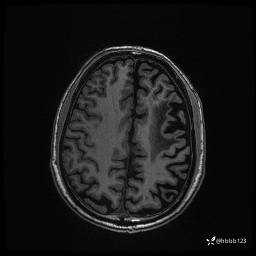

患者男,43岁。

简要病史:癫痫患者复诊,昨日发作5-6次,建议住院进一步治疗。

入院完善脑癫痫组合序列:

CUBE FLAIR横断位: